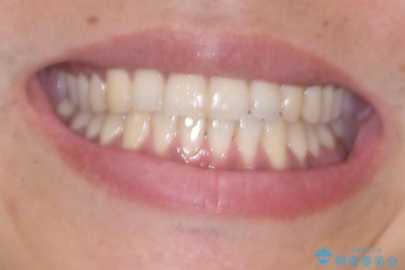

診察したところ、上下顎前歯部に軽度の叢生(ガタつき)が認められます。

目立たない装置を希望されたのでインビザライン ライトパッケージで治療を行うことになりました。